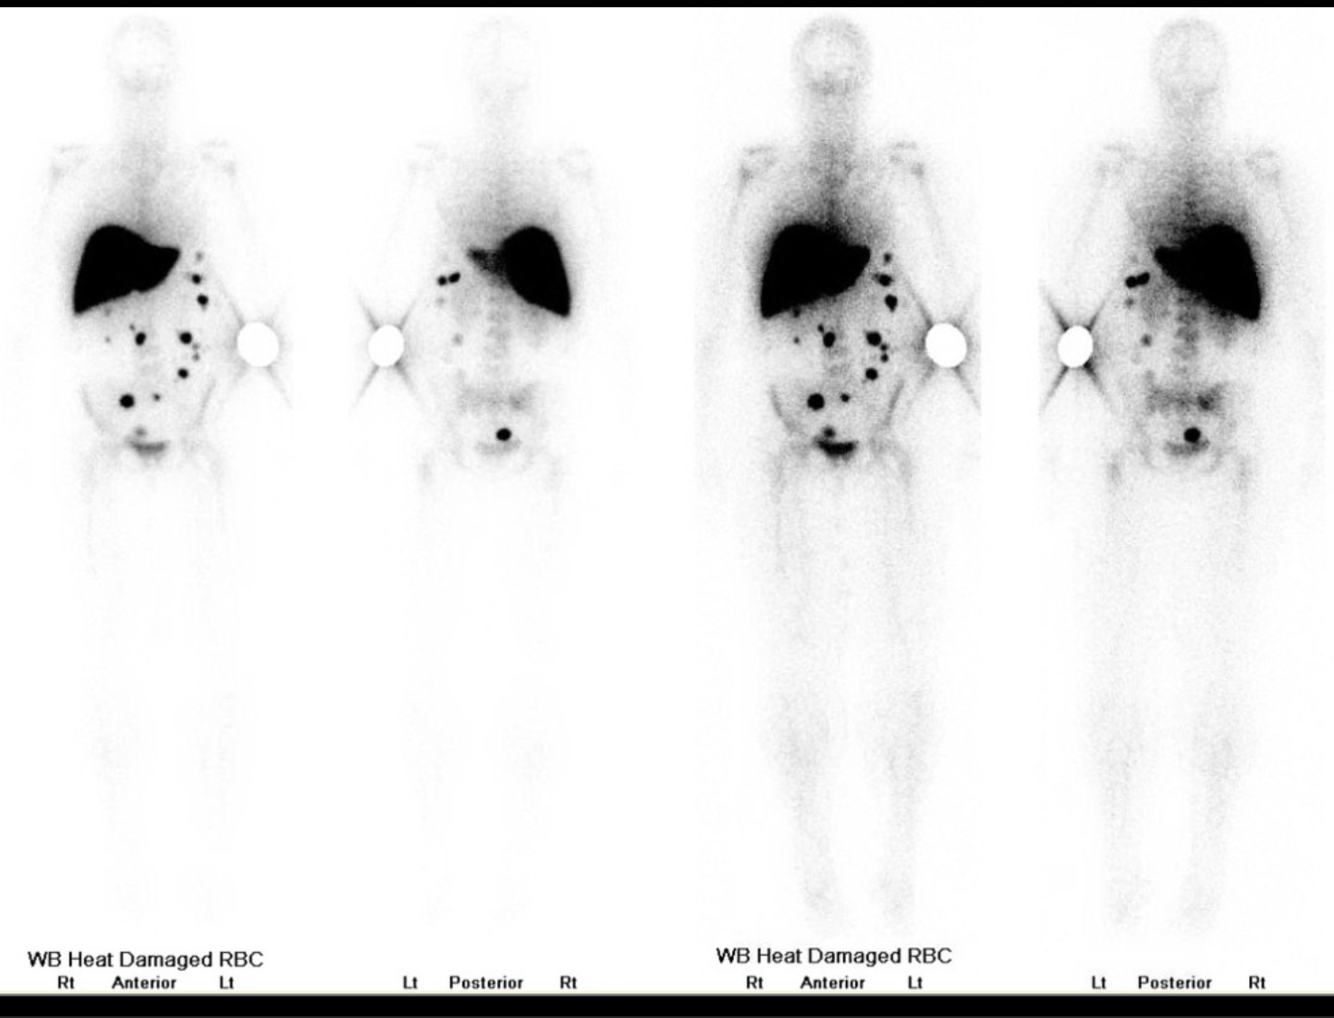

Nuclear medicine

Tc-99m sulfur colloid scan

The diagnosis can be confirmed with Tc-99m sulfur colloid scan which will demonstrate increased uptake as long as the splenunculus is at least 2 cm in diameter; improved sensitivity with hybrid imaging (SPECT-CT) is possible 7.

When Tc-99m sulfur colloid fails to confirm the presence of splenic tissue, Tc-99m-tagged heat-damaged RBC scan (Tc-99m-DRBC) with autologous erythrocytes remains the gold-standard of imaging, being capable of specifically proving splenic tissue 6,8.

Tc-99m-tagged heat-damaged RBC scan (Tc-99m-DRBC) with autologous erythrocytes shows accumulation in the abdominal cavity, consistent with intra-abdominal splenosis.

Case Discussion

Main concern for intra-abdominal lesions found on CT scan was for metastatic disease. Using heat treated RBC confirmed the functioning splenosis at the various abdominal sites.